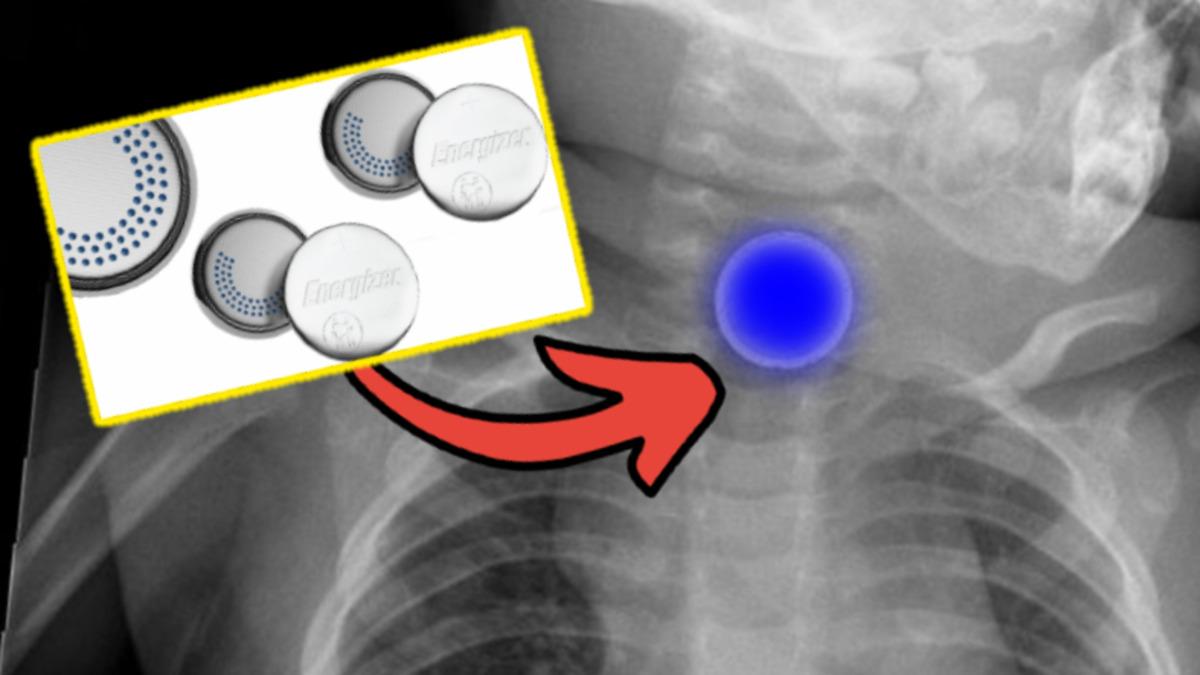

Pil, tükürük ile temas ettiğinde mavi boya salıyor ve saniyeler içinde ebeveynleri uyarıyor

Bu teknoloji, pil tükürük benzeri bir ıslaklıkla temas ettiğinde yalnızca birkaç saniye içinde mavi bir boya açığa çıkarıyor. Çocuklar, toksik olmayan kaplamanın acı tadını alırken ağızlarında bu mavilik belli oluyor. Böylece ebeveynler ağızlarına pil aldıklarını anlayarak hemen aksiyon alabiliyorlar. Energizer’ın aktardığına göre piller, aromalı bir sporcu içeceğinde bulunandan bile az seviyede gıda sınıfında bir boya içeriyor. Herhangi bir zarar olmayan bu boya, diş fırçalama veya birkaç yıkamadan sonra ağızdan kayboluyor.